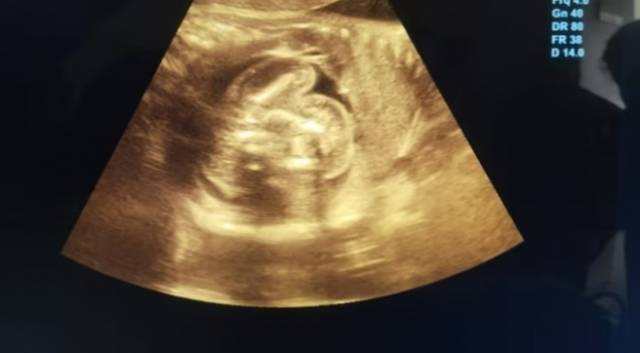

부모는 지난 7월 아기의 복부가 부풀고 식사를 제대로 하지 못하는 증상을 발견하고 병원을 찾았다. 의료진은 스캔 검사에서 종양처럼 보이는 두 개의 형태를 확인했고, 이것이 미발달 태아라고 판단했다.

아이의 어머니는 당초 세쌍둥이를 임신했으나, 두 개의 태아가 하나의 태아에 흡수되어 몸 안에서 자라고 있었던 것으로 밝혀졌다.